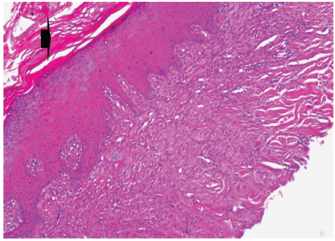

At 7 days post wounding; the inflammatory reaction was moderate and characterized by polymorphonuclear cells and macrophages infiltration with the presence of small scab covering the wound surface. Early evidence of epithelization was detected and represented by the proliferation of epidermal epithelium under the scab. There was marked thickening and hyperplastic proliferation of epidermal epithelium at the free wound edge (Fig. 6). The dermal tissue underlying the wound area showed few polymorphonuclear cells infiltration and more abundant mononuclear cells. Fibroplasia and angiogenesis were detected in the dermis and more extensive in deeper areas of the dermis which characterized by fibroblast and angioblast proliferation forming immature young granulation tissue (Fig. 7). At 14 days post wounding, the wound area was covered by a complete layer of epidermal epithelium indicating a good epithelization rate of the wound. Proliferation of cutaneous appendages was detected. The newly formed epithelium was thick and showed partial keratinization and epithelial differentiated stratum containing polyhedral keratinocyte with the appearance of keratohyalin granules in their cytoplasm (Fig. 8). The dermal tissue showed deposition of parallel well organized and interconnected collagen bundles that arranged parallel to epidermis associated with enhanced angiogenesis represented by well-developed blood capillaries (Fig. 9). At 21 days post wounding, remodeling of the formed epithelium with relatively small scar formation and mild restoration of skin appendages. Keratinized and differentiated stratum comprising the covering epithelium and the newly formed skin appendages from the basal epidermal epithelium were detected (Fig. 10). The dermal tissue revealed well-formed organized tissue consisted of parallel compact and interconnected bundles of collagen with scant angiogenesis (Fig. 11). At 28 days post wounding, well-formed scar tissue covering highly cellular organized tissue was detected (Fig. 12). The dermal tissue revealed well-arranged compact collagen bundles containing scarce blood vessels (Fig. 13).

Fig. 6. Skin of a goat from electroacupuncture group at 7 days post wounding showing early evidence of epithelization, hyperplastic proliferation of epidermal epithelium (arrow head) at the free wound edge, and moderate inflammatory cells infiltrations in the dermis (arrow), (HE ×100).

Fig. 7. Skin of a goat from electroacupuncture group at 7 days post wounding showing fibrin exudation at wound surface with dermal edema, hemorrhages (arrow) with moderate mononuclear cells infiltration associated with formation of immature granulation tissue consisted of fibroblast and angioblast forming small blood channels (arrow head), (HE ×200).